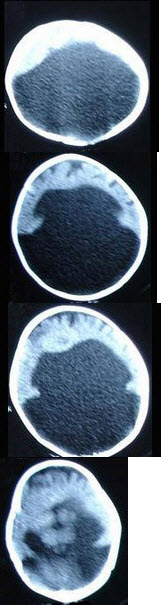

10、单项选择题

男,35岁,间歇性癫痫发作20余年,CT检查如图,最可能的诊断为()

A.表皮样囊肿

B.血管母细胞瘤

C.胼胝体发育不良

D.灰质异位

E.脑囊肿

11、单项选择题

男,12岁,抽搐、学习差,智力发育低于同龄儿童,MR检查如图,选择最可能的诊断()